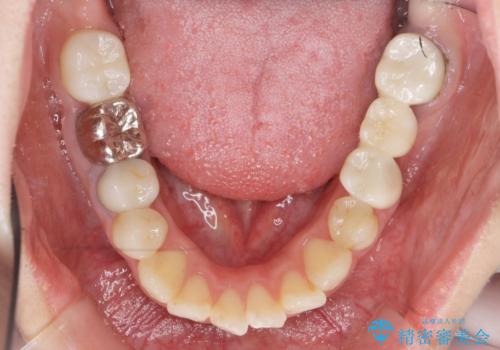

インプラント・セラミック・矯正治療を含む包括歯科診療

- 20代女性

虫歯や咬合関係・歯槽骨の吸収・根尖病変・歯の欠損・複合的な問題を一つずつ解決し、

安定した噛み合わせの構築・歯ブラシのしやすい環境の整備・歯内歯周の感染除去・造骨を伴うインプラント治療

を行い、長期的な予後を見込める口腔内環境を確立、整備して行きます。

インプラント治療の注意事項(リスク・副作用など)

- 外科手術のため、術後に痛みや腫れ、違和感を伴います

- メンテナンスを怠ったり喫煙により、お口の中に大きな悪影響を及ぼすインプラント周囲炎等にかかる可能性があります

- 糖尿病、肝硬変、心臓病等の場合、インプラント治療ができない可能性があります

- 高血圧、貧血・不整脈等の場合、インプラント治療後に治癒不全を招く可能性があります

- 自費診療(保険適用外治療)となります